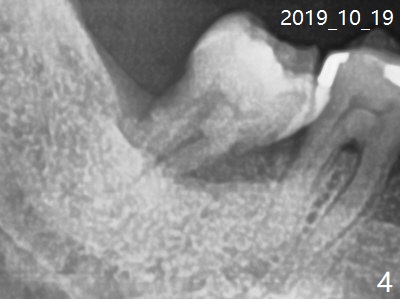

A 60-year-old man has chronic periodontitis, bruxism and malocclusion, e.g., #18 mesiolingual inclination (under occlusal trauma, Fig.1). The lingual pocket is deep with severe bone loss. After extraction, use implant positioner to gauze the size of the socket. Initiate osteotomy as mesial as possible and parallel to the 1st molar (Fig.2,3). Bone density is expected to be high. Prepare soft (1-piece) and hard (IS) tissue-level implants. The tooth remains loose 2 years later, although the patient is asymptomatic (Fig.4). Finally the tooth is symptomatic because of root tip fracture (Fig.5). Use drills with 7.3 mm stop for 4.5 or 5.0x8.5 mm implant free hand (Fig.6). The exposed implant will be covered with sticky bone (PRFx2). Prepare temporary and cemented abutments to hold bone graft in place.